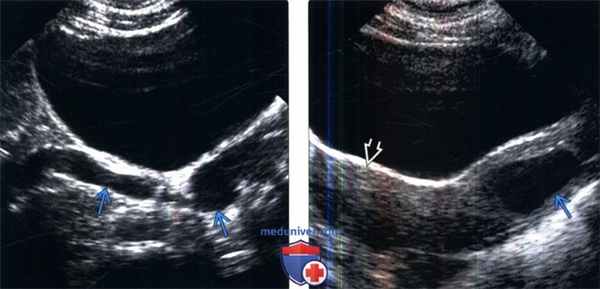

(Слева) УЗИ мочевого пузыря в продольной плоскости: извитой расширенный мочеточник, продолжающийся вне ожидаемого отверстия в треугольнике мочевого пузыря.

(Справа) УЗИ в продольной плоскости: у этого же пациента определяется кистозное образование в стенке влагалища, представляющее собой эктопическое устье расширенного и закупоренного мочеточника, дренирующего верхнюю лоханку удвоенной собирательной системы. Также визуализируется матка, которая имеет нормальные характеристики.

(Слева) УЗИ левой почки в продольной плоскости: расширенный эктопический мочеточник, медиальнее и глубже по отношению к почке. Следует обратить внимание на кистозную дисплазию части верхнего полюса.

(Справа) Микционная цистоуретерограмма: определяется рефлюкс мочи в эктопический левый мочеточник, который открывается в уретру.